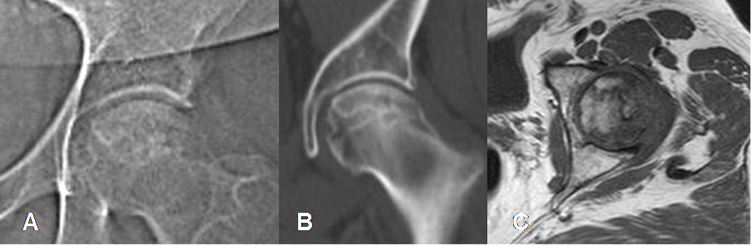

Fig 86. Osteonecrosis.

A: Rx digital AP, B: TAC reconstrucción coronal y C: RM axial en T1. Osteonecrosis que compromete mas del 50% de la cabeza femoral, con gran riesgo de colapso.